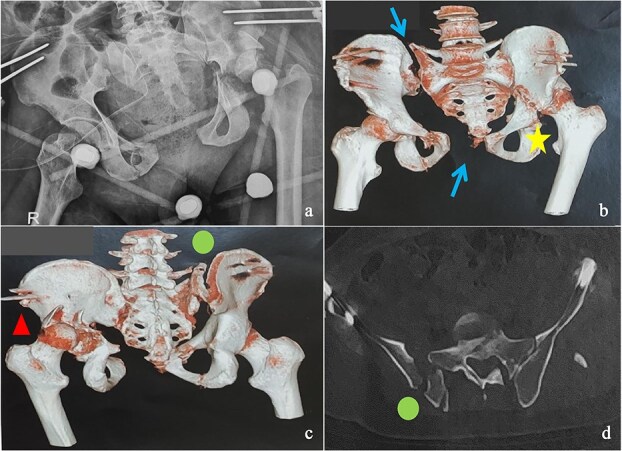

由于手术技术和策略的复杂性,骨盆环和髋臼骨折在不愈合或不愈合的晚期是一个治疗挑战。我们报告一例42岁男性患者骨盆和左髋关节外伤诊断后40天的伤害,经过长期重症监护的严重胸部外伤。影像学显示为Tile-AO B1-2骨盆骨折伴髋臼横后壁骨折和股骨头脱位。采用多路手术切除骨痂,实现复位和固定。最初的结果是有利的。10个月时,患者出现左髋关节骨关节炎并接受了原发性全髋关节置换术。在36个月的随访中,他的哈里斯髋关节评分为85分,马吉德评分为86分,并恢复了接近正常的日常活动。这些复杂的病例需要仔细规划,早期手术复位对于移位的近期骨折至关重要。

Managing pelvic ring and acetabular fractures at a late stage of malunion or nonunion is a therapeutic challenge due to the complexity of both the surgical technique and strategy. We report the case of a 42-year-old male patient with pelvic and left hip trauma diagnosed 40 days postinjury, after a prolonged intensive care stay for severe chest trauma. Imaging revealed a Tile-AO B1-2 pelvic fracture with associated transverse-posterior wall acetabular fracture and femoral head dislocation. A two-stage surgery using multiple approaches was performed to remove callus and achieve reduction and fixation. The initial outcome was favorable. At 10 months, the patient developed left hip osteoarthritis and underwent primary total hip arthroplasty. At 36-month follow-up, he had a Harris Hip Score of 85, a Majeed score of 86, and had resumed near-normal daily activities. These complex cases require careful planning, with early surgical reduction being essential in displaced recent fractures.